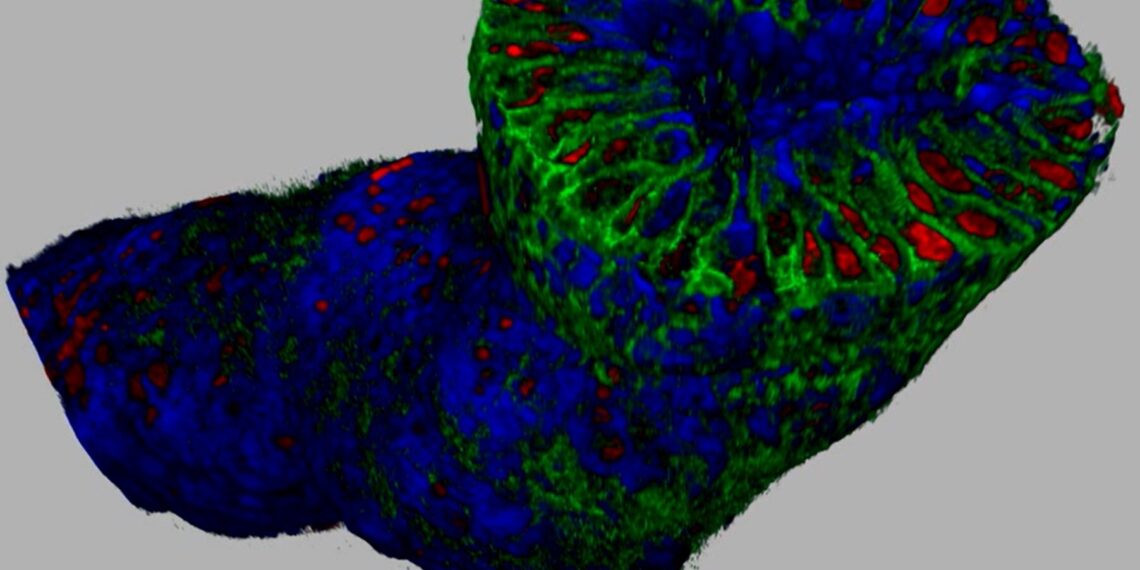

This is a 3D fluorescent-stained image of mammary ducts from a breast cancer patient. Green areas indicate drug-targeted receptors. Unlike traditional 2D pathology, this reveals the spatial distribution of receptors, reducing the risk of misjudging treatment decisions.

According to the US National Cancer Institute, breast cancer is the most prevalent form of cancer. However, the difficulty of precisely determining treatment has made the identification of HER2 expression essential. In HER2-low and HER2-ultralow metastatic breast cancer, the novel antibody-drug conjugate (ADC) Trastuzumab deruxtecan (T-DXd) has demonstrated robust efficacy over conventional chemotherapy. Yet considering HER2 spatial heterogeneity, traditional diagnostic methods have shown to be less precise than 3D pathology in detecting the presence of the HER2 protein.

In JelloX’s research collaboration with NTUH, preliminary findings indicate that more than half of the analyzed cases exhibited diagnostic discrepancies when re-evaluated using the company’s advanced 3D pathology methods. Notably, among patients initially classified as HER2-null by traditional methods, more than 66.7% were reclassified as HER2-expressing (HER2-low or HER2-ultralow) using 3D technology, thereby becoming potentially eligible for T-DXd treatment.